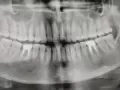

К врачу еще не обращался, пока не беспокоит. Сделал панорамный снимок (зуб помечен).

Не знаю, удалять его или нет? Их и так очень мало. Что можете сказать по фото?

Зуб однозначно удаляется по причине обширного воспалительного процесса.

Также зубы 46, 45 в консольной конструкции имеют воспаление на верхушках зубов.